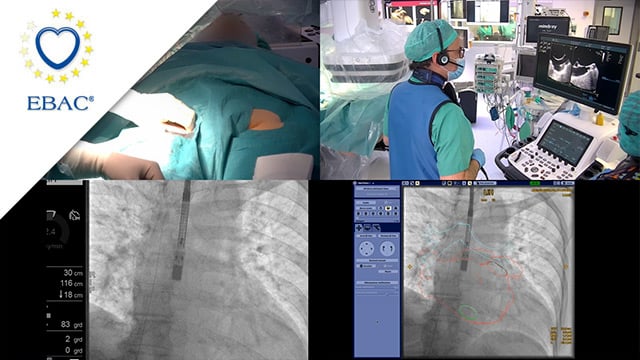

LAA closure - LIVE case

16 May 2024 – From EuroPCR 2024

A 78-year-old woman with hypertension, diabetes, obesity, and a history of pacemaker implantation in 2023, presented with retinal hemorrhage while on NACO for AF. Despite a CHA2DS2-VASC score of 5, anticoagulation was withdrawn. The operators implanted a Watchman device in the LAA via a venous right femoral...